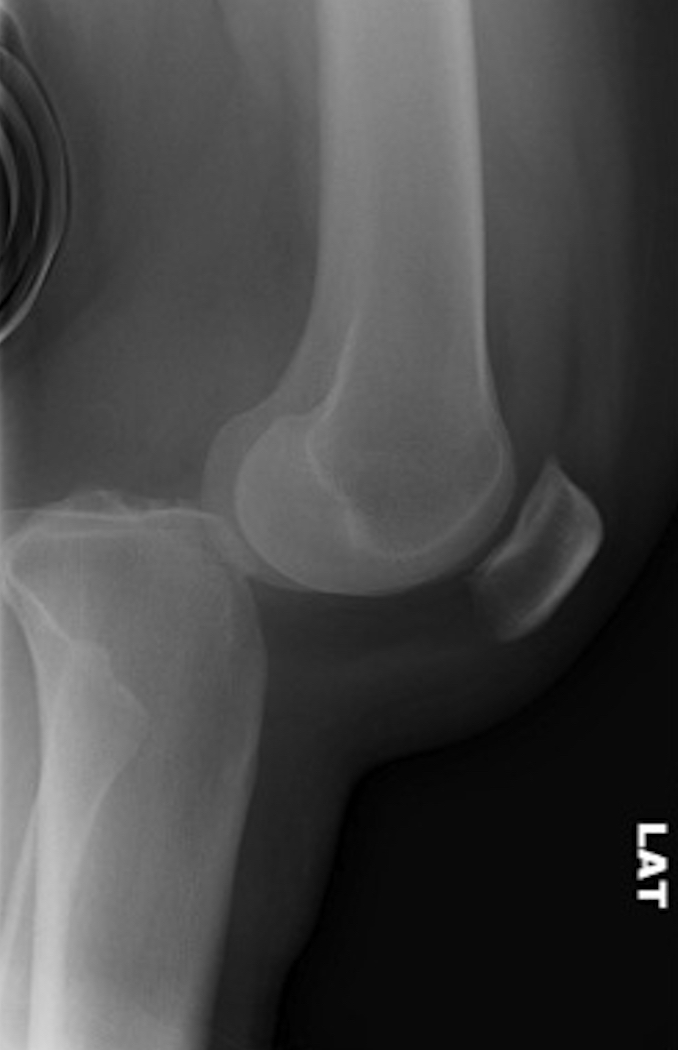

Anterior knee dislocations

Posterior knee dislocations